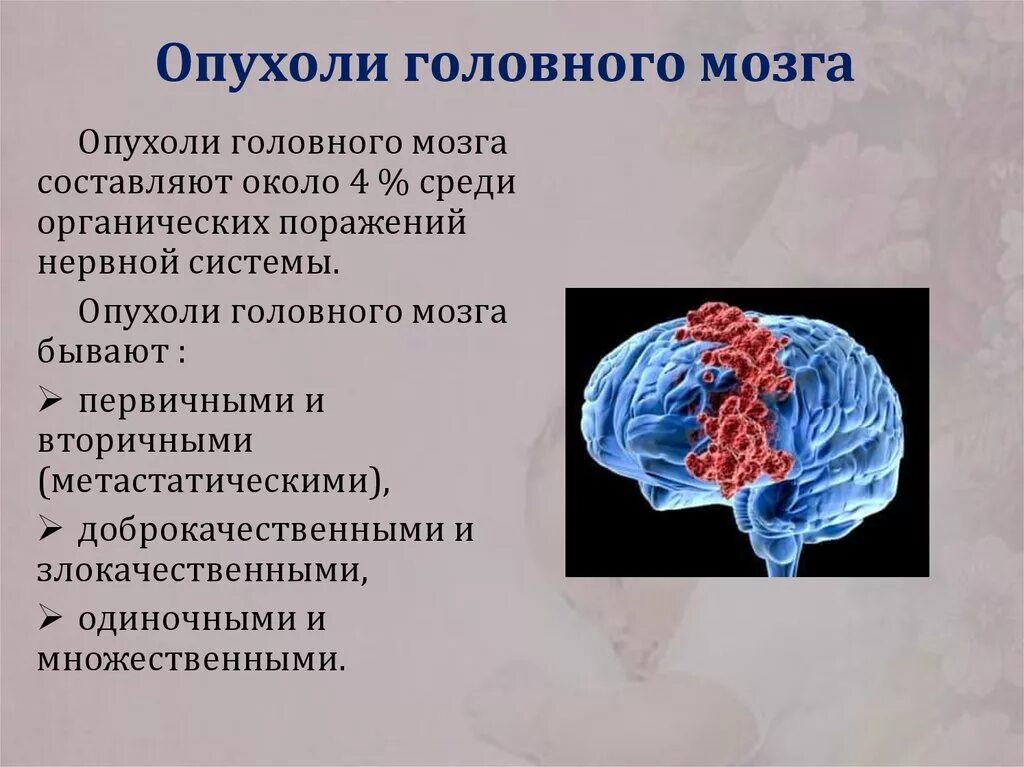

Лучевая диагностика опухолей поджелудочной железы. Методы диагностики патологии поджелудочной железы. Методы исследования поджелудочной железы. Метод исследования поджелудочной железы. Опухоль головного мозга стадии. Опухоль головного мозга симптомы. Проявление опухоли головного мозга. Степени опухолей головного мозга.

Опухоль головного мозга стадии. Опухоль головного мозга симптомы. Проявление опухоли головного мозга. Степени опухолей головного мозга. Методы исследования при опухоли головного мозга. Дополнительные методы исследования опухолей головного мозга. Диагноз кт с опухолью головного мозга. Дополнительные методы исследования при опухолях головного мозга.

Диагностика ра а желудка. РВК желудка дипгностика. Иагностика рада желудка. Методы диагностики в онкологии. Опкхолльлголовного мозга. Новообразование в головном мозге. Злокачественная опухоль головного мозга.

Опкхолльлголовного мозга. Новообразование в головном мозге. Злокачественная опухоль головного мозга. Методы диагностики опухолей. Метод диагностики опухолей. Методы выявления опухоли. Этапы диагностики опухолей.

Методы диагностики опухолей. Метод диагностики опухолей. Методы выявления опухоли. Этапы диагностики опухолей. Новообразование в головном мозге. Презентация опухоль мозга. Опухоли головного мозга презентация.

Метод диагностики желчекаменной болезни. Методы рентгенологического исследования при желчнокаменной болезни. Рентгенологические методы исследования желчного пузыря. Методы исследования больных с заболеваниями желчного пузыря. Онкология головного мозга. Раковые заболевания головного мозга.

Онкология головного мозга. Раковые заболевания головного мозга. Амебиазный абсцесс печени. Солитарный абсцесс печени. Амебный абсцесс печени кт.

Молочная железа маммография. Мастопатия на маммографии. Опухоль молочной железы маммограмма. Рик молочной железы маммографич. Опухоль головного мозга симптомы. Новообразование в головном мозге. Раковые заболевания головного мозга. Объемное образование головного мозга.

Опухоль головного мозга симптомы. Новообразование в головном мозге. Раковые заболевания головного мозга. Объемное образование головного мозга. Терминальная стадия онкологии. Опухоль грудной стенки кт. Опухоль в терминальной стадии.